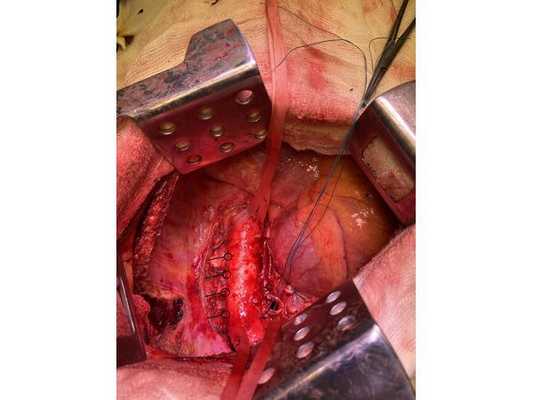

Интраоперационное фото: клипированные межрёберные артерии; аорта на тесёмочных держалках по краям зоны резекции адвентиции; культя главного бронха с провизорными швами при ушивании по Оверхольту

Проведён онкологический консилиум (Клиническая больница № 2 АО ГК МЕДСИ). Решением консилиума рекомендовано первым этапом провести хирургическое лечение в объёме нижней лобэктомии (удаления доли органа) с циркулярной резекцией левого главного бронха (удалением сегмента бронха с восстановлением целостности бронхиального дерева) или пневмонэктомии слева (полного удаления лёгкого) после интраоперационной ревизии с систематической медиастинальной лимфодиссекцией (иссечением лимфатических узлов).

- боковая торакотомия (вскрытие грудной клетки) слева;

- пневмонэктомия с резекцией адвентиции (наружной оболочки) аорты, париетальной и медиастинальной плевры и мышечной стенки пищевода;

1. В положении на правом боку с раздельной вентиляцией лёгких выполнена боковая торакотомия слева. При ревизии:

- в плевральной полости выпота (скопления жидкости) нет;

- имеются единичные сращения в области верхней доли и 6 сегмента — разделены при помощи электрокоагуляции;

- очагового поражения париетальной и висцеральной плевры нет.

- в нижней доле имеется плотная большая опухоль, подрастающая к грудной аорте и врастающая в медиастинальную плевру и средостение;

- сосуды корня лёгкого в опухолевый процесс не вовлечены;

- определяются множественные неувеличенные в размерах лимфатические узлы.

Учитывая данные интраоперационной ревизии, диагноз скорректирован: центральный местно-распространённый немелкоклеточный рак нижней доли левого лёгкого с врастанием в адвентицию аорты и ткани средостения — cT4NxM0. Принято решение о выполнении пневмонэктомии (полного удаления лёгкого).

2. Выделены и взяты на держалки верхняя и нижняя лёгочные вены, выделен ствол лёгочной артерии, который также взят на держалку. Выполнено пробное пережатие лёгочной артерии — нарушений гемодинамики (движения крови по сосудам) и гемоксигенации (насыщения крови кислородом) нет.

3. Последовательно прошиты сшивающими аппаратами и пересечены нижняя и верхняя лёгочные вены и ствол лёгочной артерии. Выявлено, что опухоль подрастает к мышечной стенке пищевода, выполнена краевая резекция мышечной стенки пищевода на протяжении 2 см.

4. Острым путём отсечён левый главный бронх, при этом обнаружено, что опухоль распространяется перибронхиально. Культя левого главного бронха реампутирована (ампутирована повторно) в пределах визуально здоровой ткани стенки бронха, до 1,5-2 см от карины трахеи (гребня хряща между разделением двух главных бронхов). Центральная часть культи левого главного бронха ушита по Оверхольту.

5. Отступив по грудной стенке от края врастания опухоли в аорты на 2 см, рассечена и отсепарована (отделена хирургически) париетальная плевра и адвентиция аорты. Аорта мобилизована по типу "ручки чемодана" и взята на тесёмочные держалки выше и ниже места врастания опухоли.

6. Скелетизируя грудную стенку и аорту, с перевязкой левых межрёберных артерий, на участке рёбер 4, 5, 6 и 7 выполнена полуциркулярная резекция адвентиции аорты, мягких тканей грудной стенки с париетальной плеврой и тканей средостения.

7. Пневмонэктомия. Проверка аэростаза (герметичности) под уровнем жидкости — просачивания воздуха в области культи бронха нет.

8. Выполнена лимфодиссекция из области лёгочной связки, области бифуркации трахеи (места её разделения на главные бронхи), аортального окна, левого трахеобронхаильного угла и нижних паратрахеальных лимфатических узлов слева. Проверка гемостаза — сухо.

10. В плевральную полость заведён толстый силиконовый дренаж. Послойное ушивание раны, рёбра сведены тремя перикостальными швами. Наложена асептическая повязка.